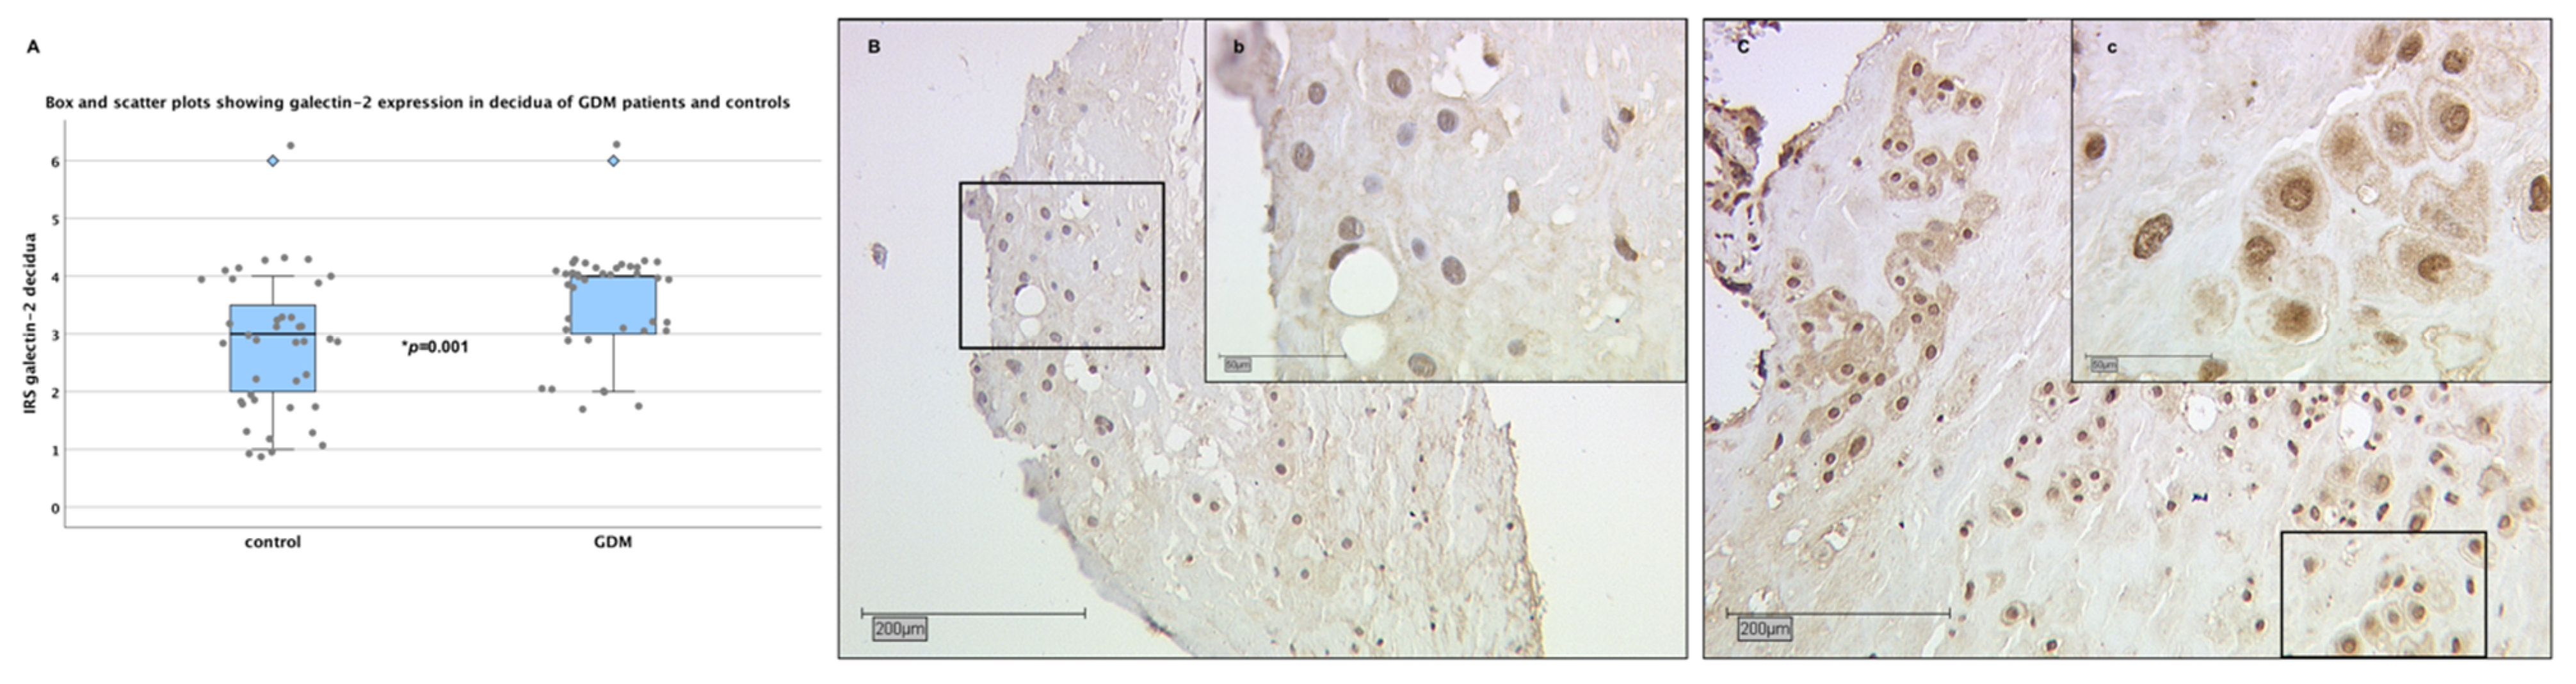

2.3. Galectin-2 Expression Is Upregulated in the Maternal Decidua of GDM Placentas